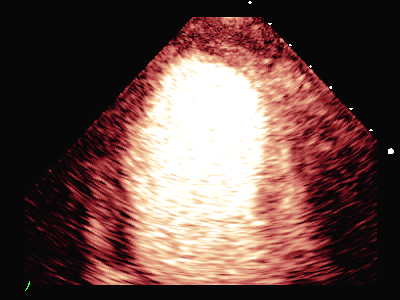

超声负荷造影提示:

负荷前左室壁未见明确节段性运动异常,左室各节段心肌灌注充盈良好。

平板负荷量达89%时,该时患者心率157次/分,出现短阵性室性心动过速,即刻超声造影检查显示:负荷后左室前间隔中段、室间隔心尖段、侧壁中段、心尖段、下壁心尖段、前壁心尖段及心尖帽运动减弱。室间隔心尖段及心尖帽心肌灌注稀疏。

患者休息后检查:左室壁未见明确节段性运动异常,左室各节段心肌灌注充盈良好。